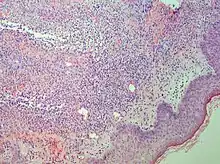

Interface dermatitis with lichenoid inflammation

| Main conditions[2] | Characteristics | Micrograph | Photograph |

| Generally/Not otherwise specified | Typical findings:[2]

|

| Lichen planus | Irregular epidermal hyperplasia with a jagged “sawtooth” appearance, compact hyperkeratosis or orthokeratosis, foci of wedge-shaped hypergranulosis, basilar vacuolar degeneration, slight spongiosis in the spinous layer, and squamatization. The dermal papillae between the elongated rete ridges are frequently dome shaped. Necrotic keratinocytes can be observed in the basal layer of the epidermis and at the dermal-epidermal junction. Eosinophilic remnants of anucleate apoptotic basal cells may also be found in the dermis and are referred to as “colloid or civatte bodies”. Whickham striae are usually seen in the areas of hypergranulosis. Vacuolar degeneration at the basal layer may be noted leading to focal subepidermal clefts (Max Joseph spaces). Squamatization occurs as a result of maturation and flattening of cells in the basal layer. It happens in areas of marked hypergranulosis with prominence of the sawtooth pattern of rete ridges. Wedge-shaped hypergranulosis can occur in the eccrine ducts (acrosyringia) or hair follicles (acrotrichia). In the hypertrophic subtype, the associated hyperkeratosis, parakeratosis, hypergranulosis, papillomatosis, acanthosis, and hyperplasia markedly increased with thicker collagen bundles forming in the dermis. Moreover, the rete ridges are more elongated and rounded as opposed to the typical sawtooth pattern. In atrophic LP, loss of the rete ridges and dermal fibrosis is prominent. In vesiculobullous LP, the disease progression is quicker. Hence, some of the distinctive features such as hyperkeratosis, hypergranulosis, or dense lymphocytic dermal-epidermal infiltrate may not be present. LP lesion may resolve with residual hyperpigmentation caused by a persistent increase in the number of melanophages in the papillary dermis.[9] | ![]() | ![]() |